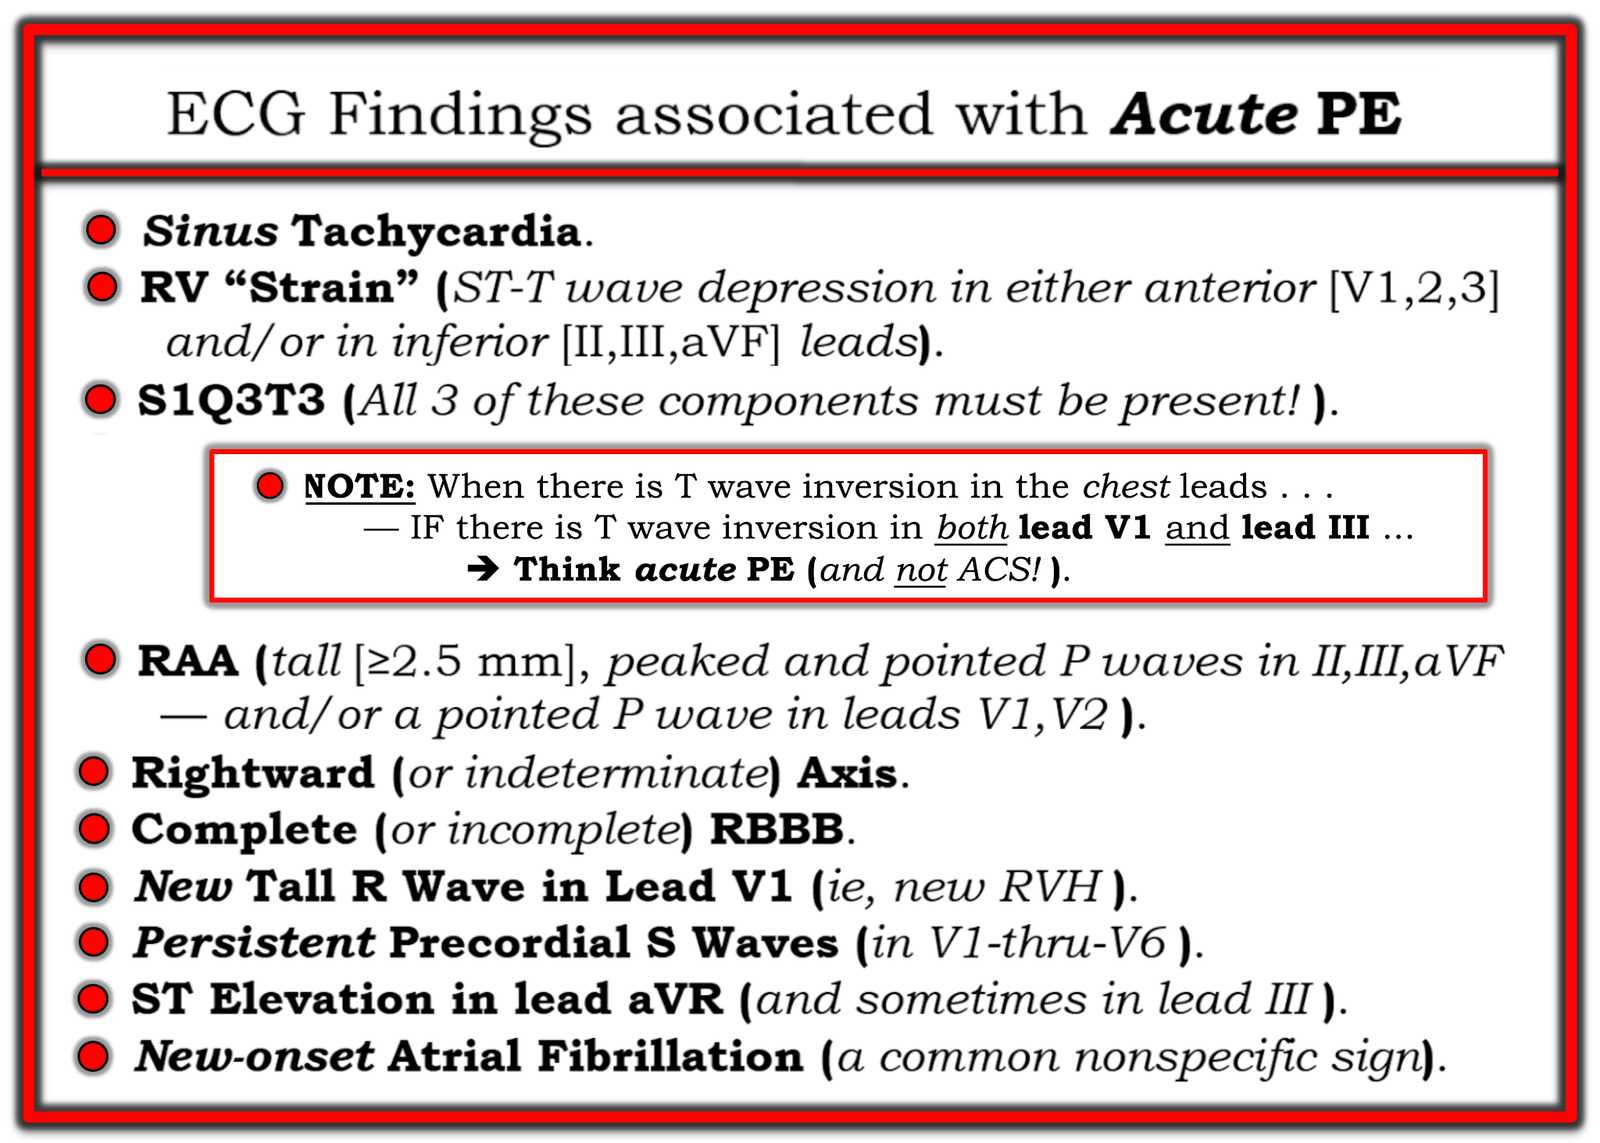

We’ve reviewed the ECG clues to acute PE in those more than 20 links that Dr. Meyers’ lists above. I found today’s initial ECG interesting — in that most of the time, the ECG diagnosis of acute PE is highlighted by more than just a couple of the ECG Findings that I list below in Figure-2.

- For example, in today’s initial ECG (that I’ve reproduced and labeled in Figure-1) — there is no sinus tachycardia — and no right axis, RAA, incomplete or complete RBBB, tall R in lead V1, persistent precordial S waves, ST elevation in lead aVR or AFib.

PEARL (as per Drs. Meyers and Smith): When there is T wave inversion in the chest leads — IF there is T wave inversion in both lead V1 and lead III ==> Think acute PE (and not ACS! ).

Figure-2: ECG Findings associated with acute PE.